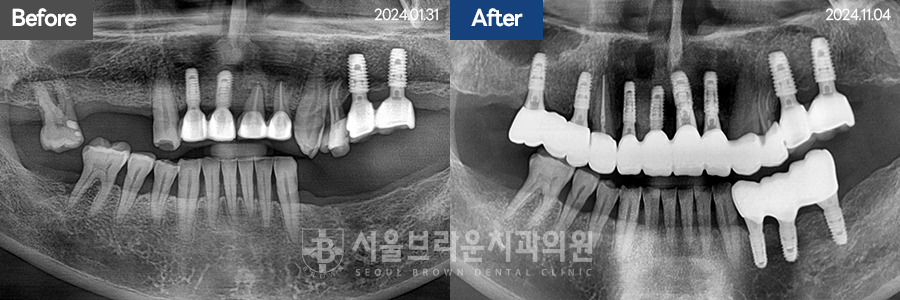

임플란트 | 50대 / 남 / 상하악임플란트

50대 / 남 / 상하악임플란트